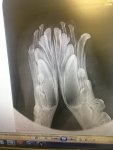

The area will still be sore, the remains of the tooth disintegrated as the vet tried to take it out, so more bone was cut away to remove the tooth safely and not disturb the capsule underneath. 4 months is difficult as ALL she wants to do is chew and carry things around, poor thing.